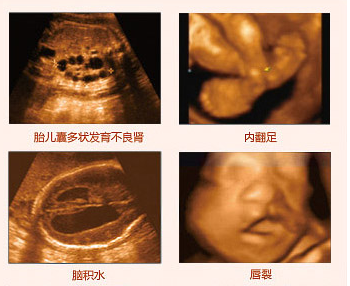

四維彩超排畸圖像

莆田盛興醫(yī)院引進(jìn)的美囯GE四維彩超,擁有當(dāng)今超聲發(fā)展較前沿的技術(shù),拓展了超聲臨床應(yīng)用范圍。美囯GE四維彩超能夠多方位、多角度地觀察宮內(nèi)胎兒的生長(zhǎng)發(fā)育情況,為早期診斷胎兒先天性體表畸形和先天性心臟疾病提供準(zhǔn)確的科學(xué)依據(jù)。不僅能夠發(fā)現(xiàn)體表畸形,同時(shí)能夠?qū)崟r(shí)的觀察人體內(nèi)部器官的動(dòng)態(tài)運(yùn)動(dòng)。可以檢測(cè)和發(fā)現(xiàn)各種異常,從血管畸形到遺傳性綜合征等。推選閱讀 四維彩超可以排查胎兒哪些畸形

超聲科醫(yī)生介紹說(shuō),四維彩超除了能給肚中的寶寶拍攝"0歲寫真",還能為胎兒檢查各器官的發(fā)育情況,為診斷胎兒先天性體表畸形,為先天性心臟疾病提供準(zhǔn)確的科學(xué)依據(jù)。為了孩子的健康、為了家庭的幸福,建議您選擇安全系數(shù)高、診斷技術(shù)、醫(yī)生有保障的醫(yī)院做四維彩超排查。